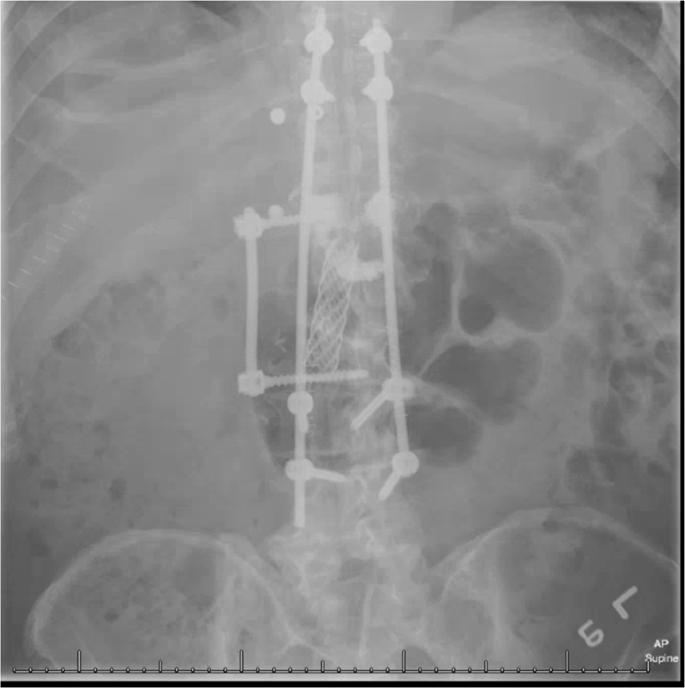

At the 2-month follow-up, he remained neurologically intact, but continued to have functionally limiting pain. A repeat MRI demonstrated a psoas and paravertebral abscess with evidence of continued vertebral collapse. An image-guided bone biopsy confirmed the presence of M. abscessus and Propionibacterium acnes. Per the recommendations of the ID-team, he was started on Rocephin, then transitioned to a multi-agent regimen, including tigecycline, amikacin, meropenem, and oral-linezolid. After a completed course of antibiotics, he still continued to demonstrate clinical signs of infection with persistent pain. Again, advanced imaging confirmed progression of disease. He underwent an anterior T12-L2 corpectomy and debridement with instrumented fusion, as well as a posterior T9-L4 instrumentation and fusion (Fig. 3). Repeat AFB culture and smear redemonstrated M. abscessus. Postoperatively, he was placed on a regimen of amikacin, azithromycin, tigecycline, and meropenem.